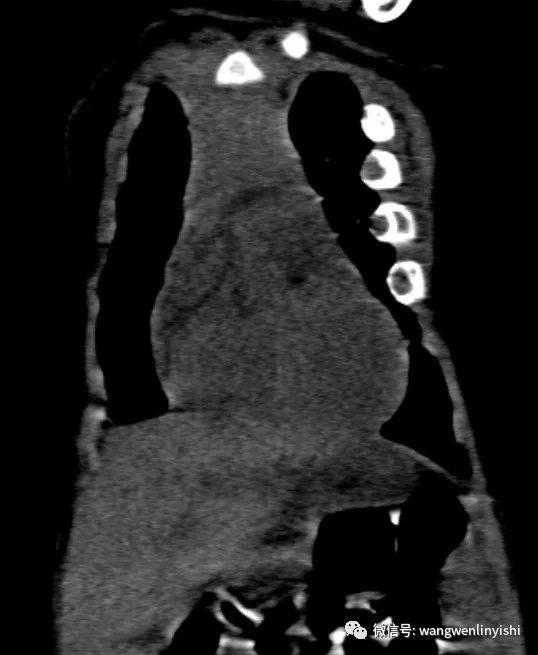

The patient, a nine-month-old infant, exhibited a chest wall abnormality along with pronounced breathing difficulties and hypoxia shortly after birth. After a series of examinations, he was diagnosed with asphyxiating thoracic dystrophy(ATD). Due to his critical condition, the child has been hospitalized for emergency resuscitation multiple times.

The infant is breathing rapidly, displaying distinct retractions in the suprasternal notch, supraclavicular fossae, and intercostal spaces (three concave signs). The chest appears narrowed, and there are visible depressions on both sides.